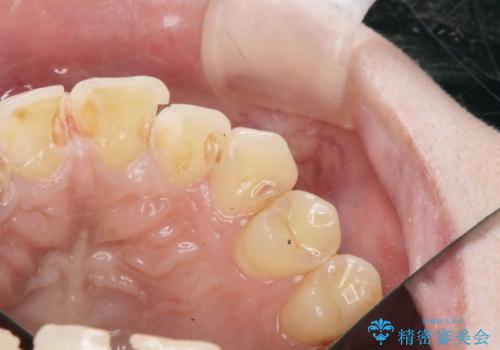

- 神経をとった前歯の変色や、前歯の充填物の変色が大きくなってきたので審美性の改善を求めて来院されました。

充填物や充填物下に再発した虫歯を丁寧に除去し、セラミッククラウンによる審美性の改善、虫歯治療を計画します。

レジン修復による充填は、劣化し、色調の変化による審美障害が生じることが多々あります。

ある程度の大きさになった充填物は、劣化の少ないセラミッククラウンにすることで色調の劣化を抑え、審美性を保つことができます。